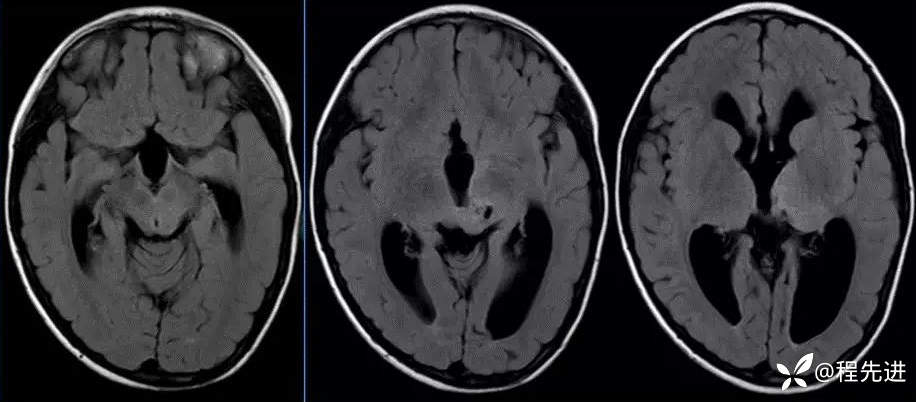

MR